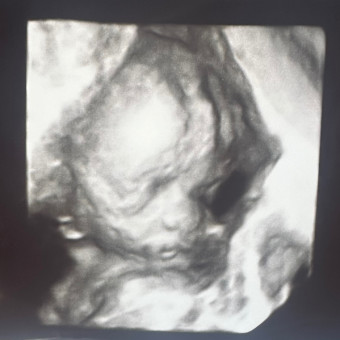

Baby Janots

Stephanie & Joseph Janots

Middletown, NY

March 23, 2026